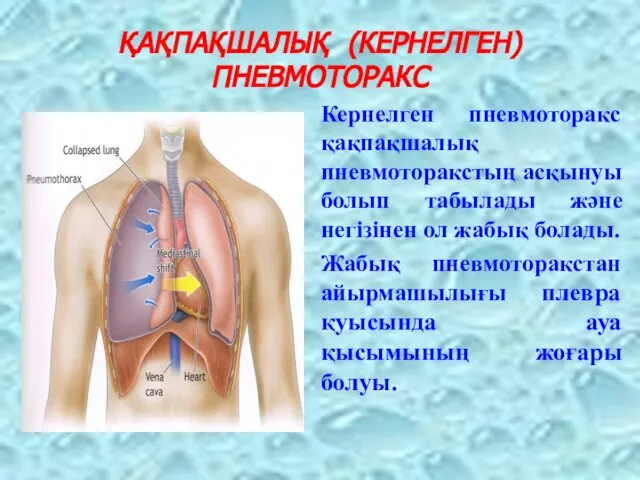

Схемы дыхания: Пневмоторакс на изображениях